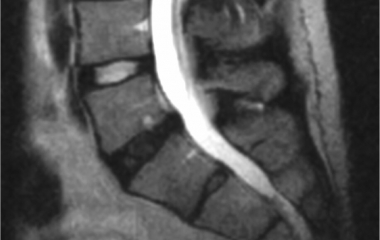

Degenerative disc disease (DDD)

Degenerative disc disease, frequently referred to as DDD, is a term that describes changes in the spinal disc occurring with age. Let us look at those changes, whether they may be the source of pain, and what treatments are available.